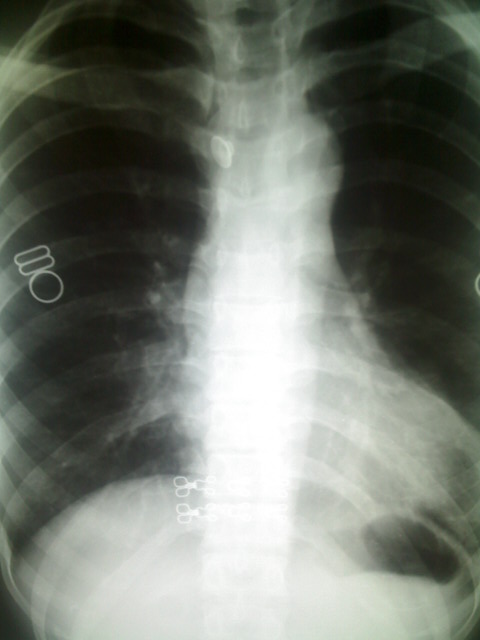

标题: X5295:大家看看,是肺上病变还是心脏上的。

女,23岁,体检。

室壁瘤?肺部占位?肺疝?建议侧位片或ct检查。

哪里?是心尖部吗?应该是心脏与肋骨、乳房的重叠形成的构成影。心右缘肺野密度增高,考虑肺心动脉,不除外肺部病变,建议侧位或ct

考虑左下肺病变;建议行ct扫描检查。

透视下,病灶随心脏搏动,外缘不光整。